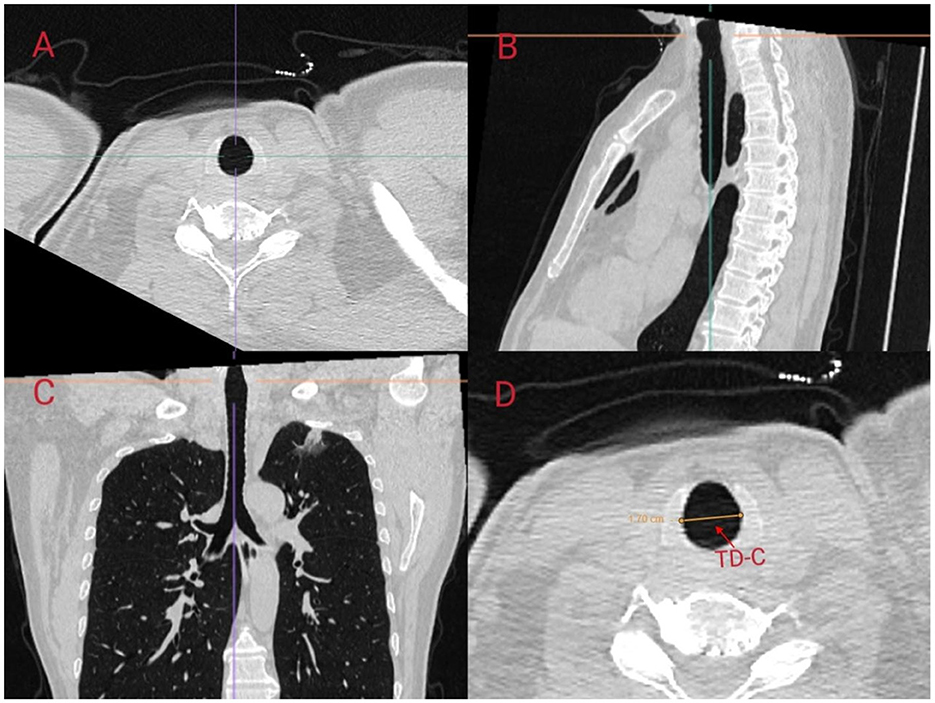

We referred to the ISO 16628:2022 standard for specific parameters of the double-lumen endotracheal tubes. The use of right-sided DLTs may lead to an increased incidence of complications, such as intraoperative hypoxemia and postoperative atelectasis, due to the potential obstruction of the orifice of the right upper lobe bronchus. In contrast, left-sided DLTs are generally considered to have a higher safety profile and are thus the preferred choice for thoracic anesthesia (11). Therefore, in this study, we aimed to predict the appropriate size for left-sided DLTs. In a study conducted by Mathew et al., the accuracy of predicting the size of left-sided DLTs by measuring the transverse diameter of the cricoid cartilage using CT was 97.5%, which was significantly superior to the 75% accuracy achieved using traditional methods based on height and gender (12). Other studies have indicated that the diameter of the left bronchus is also of significant importance in predicting the appropriate size of left-sided DLTs (13). In this study, we predicted the size of left-sided DLTs in patients by measuring the transverse diameter at the level of the cricoid cartilage (TD-C) on CT scans and calculating the equivalent circular diameter (ED-C) of the left bronchus. We followed the measurement methodology outlined by Shiqing et al. (14) in which anesthesiologists trained by radiologists utilized the MPR module of the Carestream PACS software to perform multiplanar reconstruction and measurements of the patients' trachea using axial, sagittal, and coronal slices. The inclination of the cricoid cartilage and left bronchus was adjusted to obtain strictly orthogonal slices (Figures 2, 3).

Figure 2. Scanning the left bronchus using multi-planar reconstruction (MPR) in Carestream PACS software. MPR of the cricoid cartilage was performed using (A) axial, (B) sagittal, and (C) coronal slices. The oblique angle of the transverse diameter of the cricoid cartilage was corrected in three dimensions to obtain strictly orthogonal cuts along the axis of the cricoid cartilage. The transverse diameter of the cricoid cartilage (TD-C) was measured using electronic calipers on the MPR image at the lower border of the cricoid ring (D).